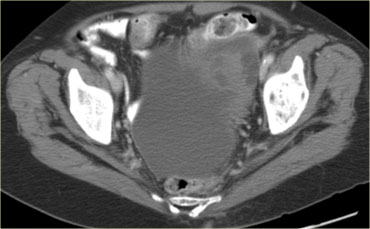

Trường hợp tiếp theo là siêu âm qua thành bụng cho thấy một khối nang đa thùy bên trái.

Hình ảnh này gợi ý u nang tân sinh buồng trứng nhưng không xác định được buồng trứng.

CT trên cùng bệnh nhân cho thấy một khối nang đa thùy tiếp giáp bàng quang, có liên quan đến tĩnh mạch buồng trứng trái (mũi tên).

Có các vách ngăn dày và thành dày không đều.

Dựa trên hình ảnh CT này, không thể phân biệt giữa tổn thương buồng trứng lành tính như u nang tuyến xơ và tổn thương buồng trứng ác tính.

Tổn thương được phẫu thuật cắt bỏ và kết quả giải phẫu bệnh xác định là u nang tuyến xơ.